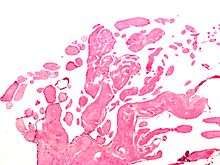

A subset of the primary tumors of the heart are tumors that are found on the valves of the heart. Tumors that affect the valves of the heart are found in an equal distribution among the four heart valves.[1] The vast majority of these are papillary fibroelastomas. Primary tumors of the valves of the heart are more likely to occur in males. While most primary tumors of the valves of the heart are not malignant, they are more likely to have symptoms related to the valve, including neurologic symptoms and (in a few cases) sudden cardiac death.